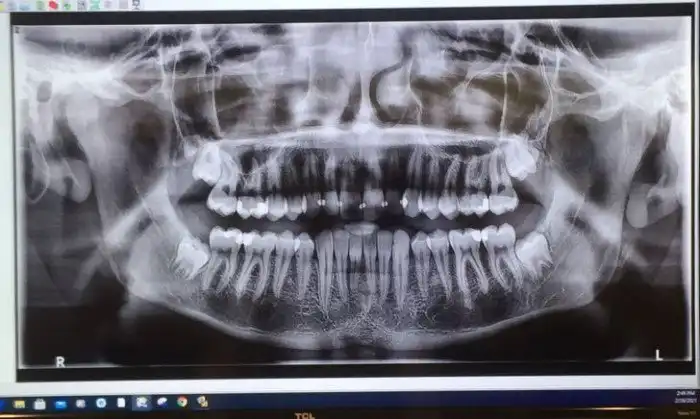

18. «Завтра мне будут удалять 6 зубов мудрости»